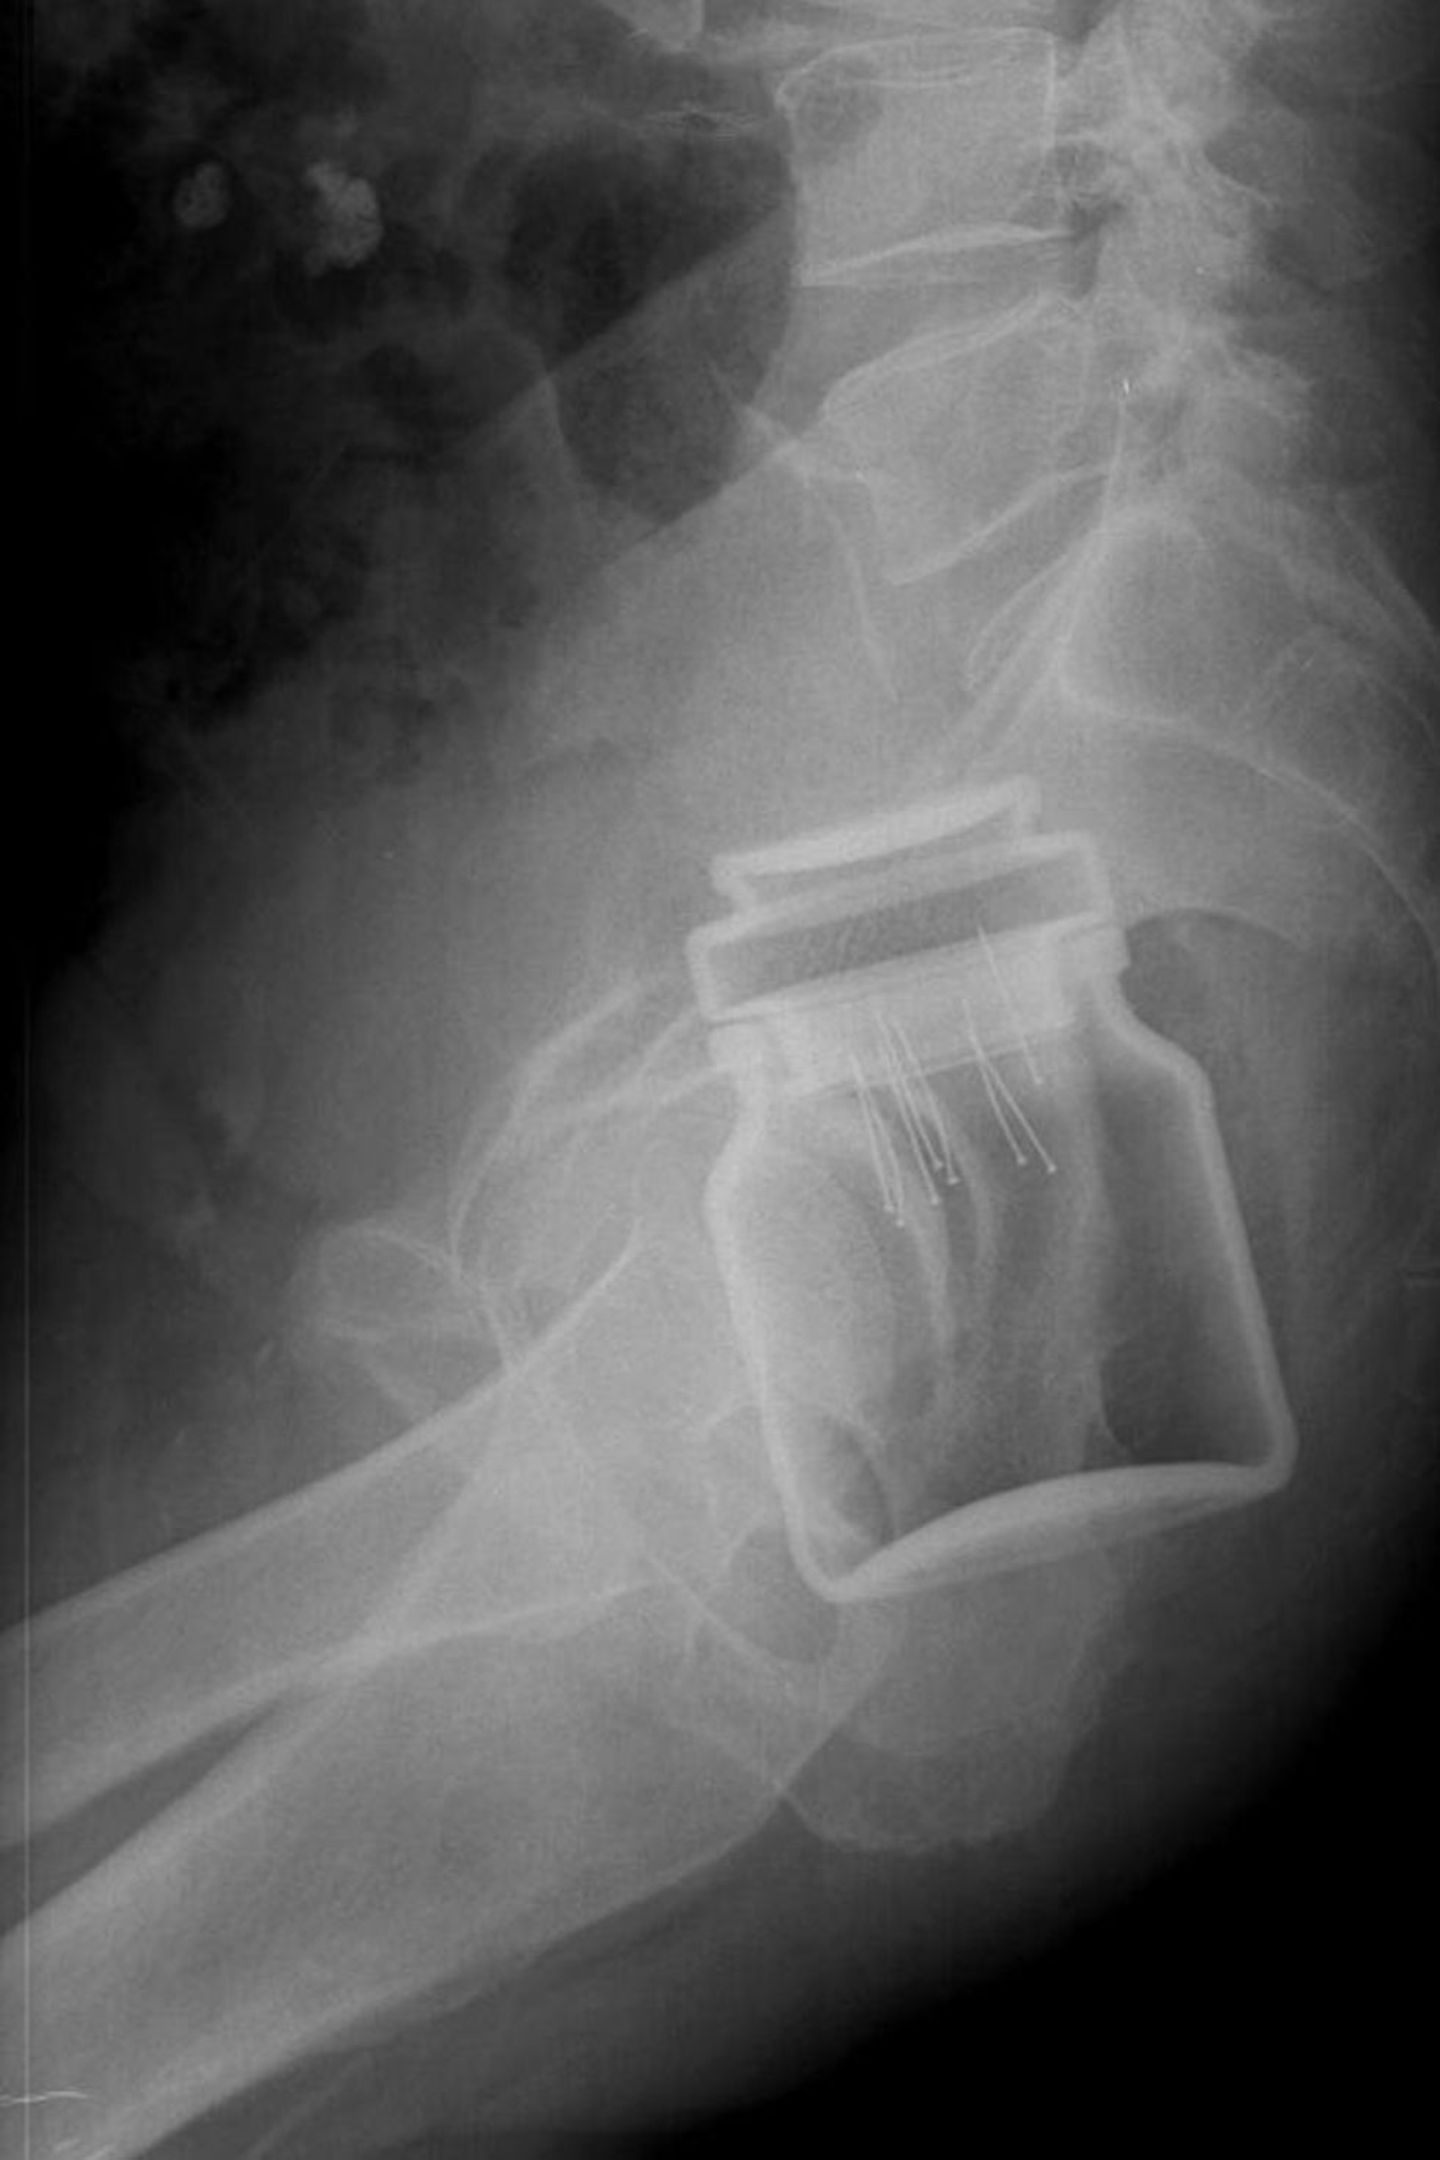

• Vom Dildo bis zur Orange: Was Ärzte auf Röntgenbildern entdecken

Unglaublich aber wahr, hier hängt eine Kaffeedose fest.